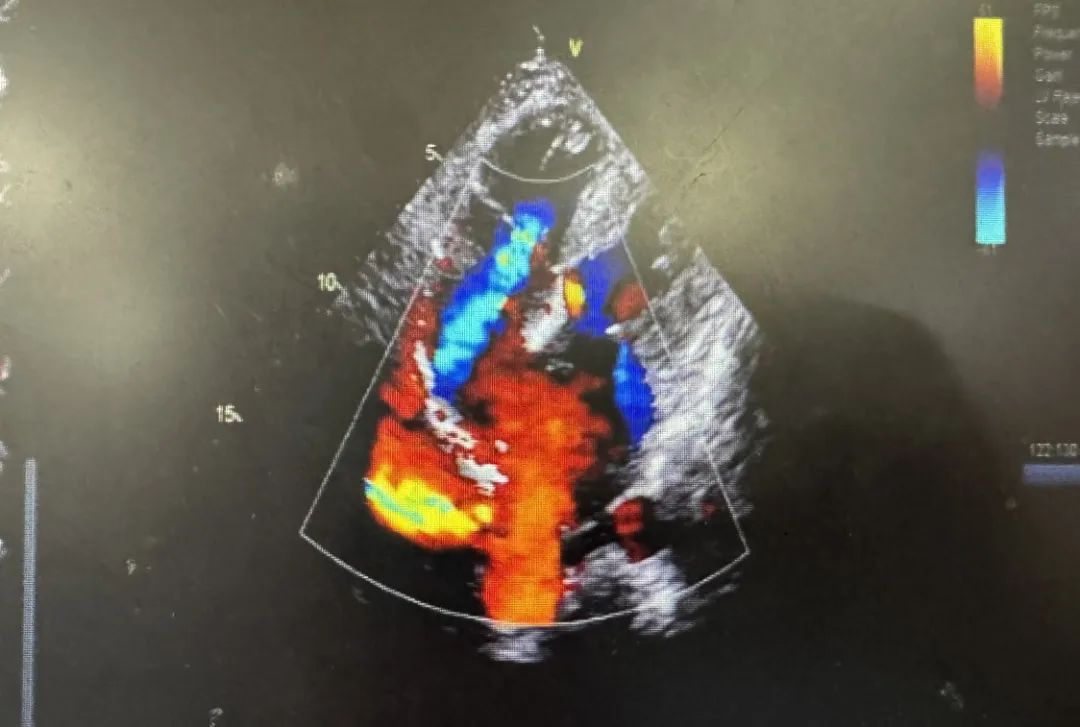

患者为 50 岁女性,因三年前头晕症状反复发作,近一个月双下肢水肿来院就诊。检查发现,患者患有先天性房间隔缺损与动脉导管未闭,还有个棘手的问题是患者合并了先天性下腔静脉肝段缺如。

常规介入封堵手术是从股静脉为路径顺着下腔静脉将封堵器送置病变部位。而患者先天性下腔静脉肝段缺如,导致微创封堵的直线路径受阻,常规路径无法到达房缺及动脉导管未闭位置。

由于患者的罕见病情,心脏大血管外科董啸教授团队反复斟酌、深入探讨。经过讨论,王利军博士提出以颈部为穿刺口,选择上腔静脉为路径送入封堵器来完成这次介入手术。这一方案既可有效避免开胸手术引发的其他并发症,又能通过微创一次性解决两个心脏问题。